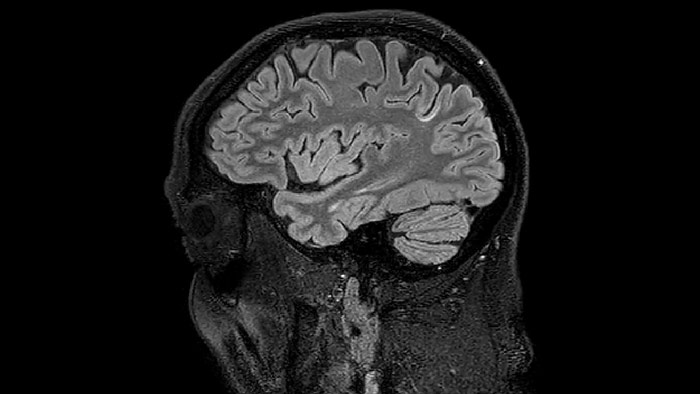

Dr. Rauscher says, “For MWI we perform 3D T2 with 32 or more echoes. This used to take a long time, but with Compressed SENSE we can decrease this to ten minutes for the whole head. Because of the large field of view (FOV) on the readout direction, we even get information from the brainstem, which we previously missed when we were using the GRASE approach. Having the whole head scan is nice because it has spatial resolution, orientation and FOV that are comparable to the standard 3D clinical MS scans, including the FLAIR and 3D T2, and a 3D T1 for brain volume.”

T1 - weighted

Myelin water imaging - T1 weighted

Myelin water imaging (echo 1)

Myelin water imaging with SENSE

Myelin water imaging with Compressed SENSE

T1 - Weighted, Myelin Water Fraction Superimposed

MWI Spinal cord coverage

Spinal cord coverage

MWI Smaller, more isotropic voxels

Smaller, more isotropic voxels

MWI Excellent detail in quantitative maps

Excellent detail in quantitative maps

Images courtesy of Adam Dvorak, Department of Physics and Astronomy, University of British Columbia